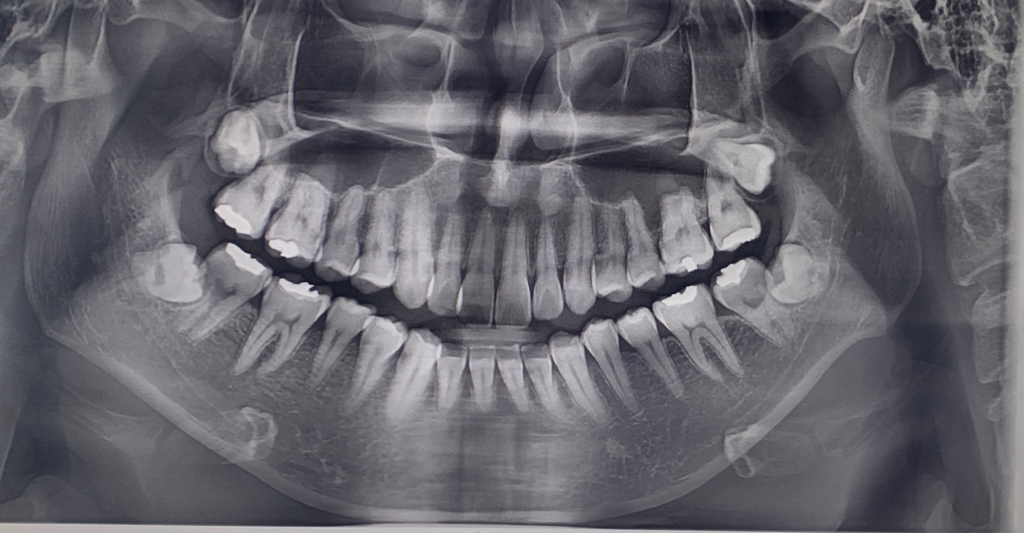

1. 첫번째가 2년전 두번째 사진이 올해찍은 엑스레이인데요 현재 나이가 27살인데 심미목적으로 치아교정을 진행중입니다.

• 1번 째 사진

아래쪽 엑스레이는 약간 잘못나온것처럼 보입니다. 그걸 감안해서보더라도 치근흡수가 많이 일어 난거 같지는 않습니다.

4. 파노라마 사진은 왜곡도 많이 되어 있고 아래 앞니가 앞으로 기울어져 있을 경우(flaring) 아주 짧게 보이는 경우도 있습니다. 따라서 아래 앞니의 각도가 어떤지 실제 모습을 봐야 정확히 알 수 있습니다. 아래 앞니 각도가 정상이라는 전제하에 치근은 평균보다 다소 짧아 보입니다.